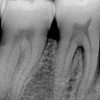

Luukadu agressiivse parodontiidiga patsiendil

Agressiivset parodontiiti iseloomustab puberteedieas või 20-ndates algav igemete kinnitus kudede ja alveolaarluu hävimine. Lokaliseerunud vormi puhul on esmased kolded esimeste jäävmolaaride, esimeste premolaaride ja lateraalsete intsisiivide piirkonnas.

Iseloomulik on progresseeruv hamba kinnituskudede kadu koos sügavate taskute moodustumisega ning väljendunud hammaste liikuvus ning reast nihkumine.